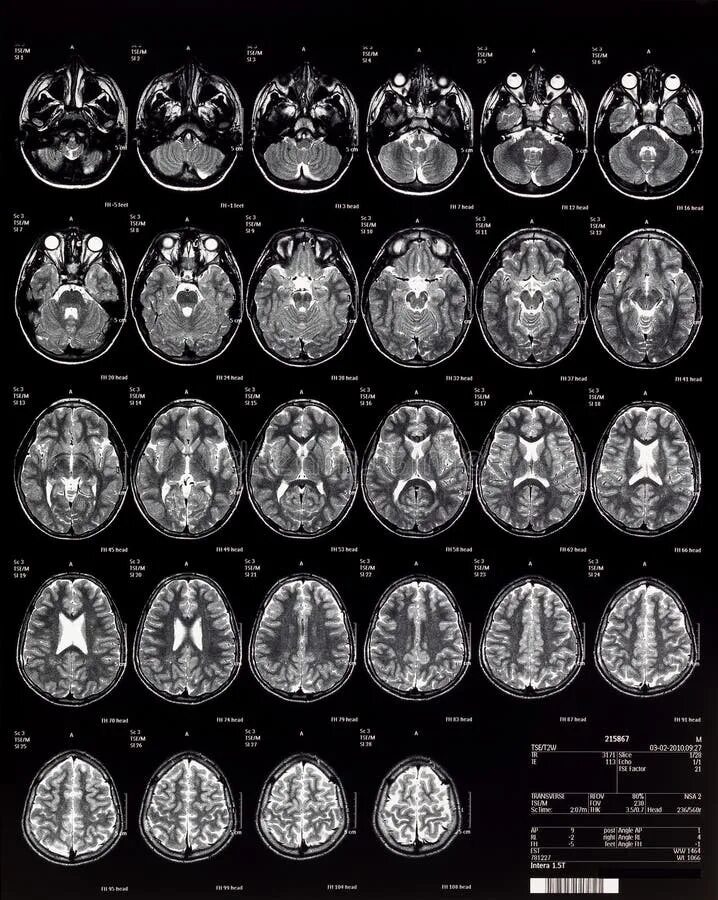

Кт с какого возраста можно делать ребенку